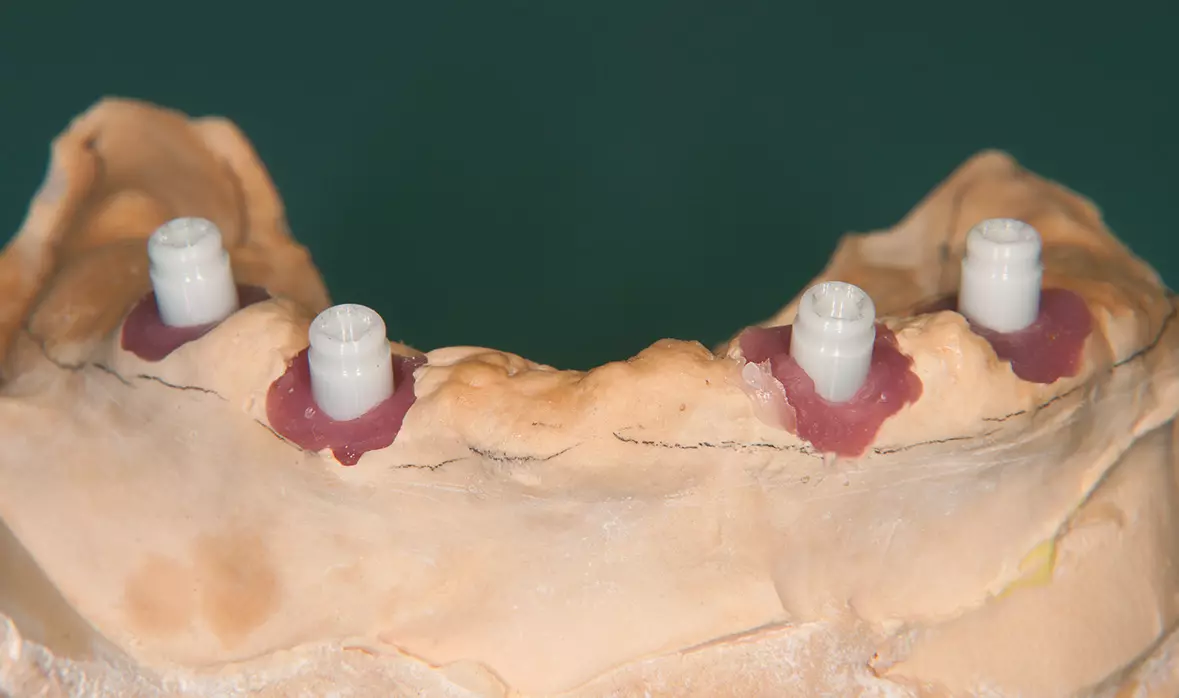

Abb. 24: Die Docklocs® Zirkon Abutments aus Zirkondioxid mit Vicarbo-Schraube. Dr. Michael Leistner

Abb. 24: Die Docklocs® Zirkon Abutments aus Zirkondioxid mit Vicarbo-Schraube.

Abb. 25: Aufgeschraubte „Snap-on“-Attachments auf dem Modell. Dr. Michael Leistner

Abb. 25: Aufgeschraubte „Snap-on“-Attachments auf dem Modell.